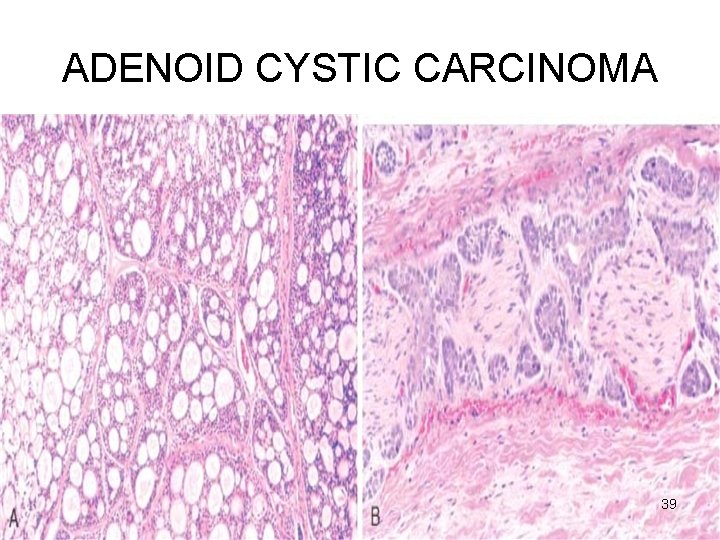

ADENOID CYSTIC CARCINOMA Microscopy • Small cells with dark compact nuclei, scanty cytoplasm • Arranged in tubules, solid, cribriform • SPACES BETWEEN CELLS FILLED WITH HYALINE MATERIAL – basement membrane material • Perineural invasion - pain 38

ADENOID CYSTIC CARCINOMA 39

ADENOID CYSTIC CARCINOMA 41